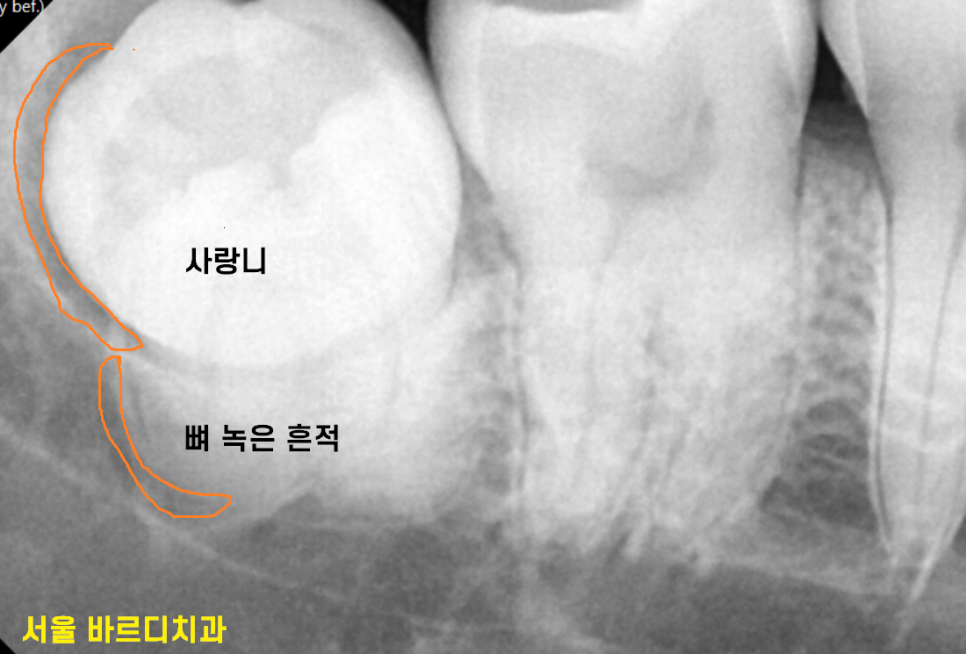

사랑니 주변으로 잇몸뼈도 녹아있어서

좋을게 없었거든요~

3D-CT를 통해 사랑니와 신경이 근접해 있는 정도

어떻게 발치할 것인가

직접 그리면서 보여드렸죠.

화살표 방향으로 뽑아낼꺼다...

저희 계획중 일부입니다.